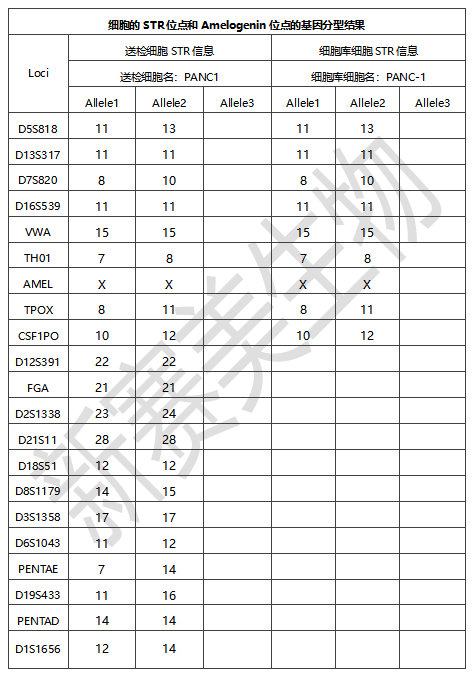

细胞STR检测图谱:

细胞样品分型结果: